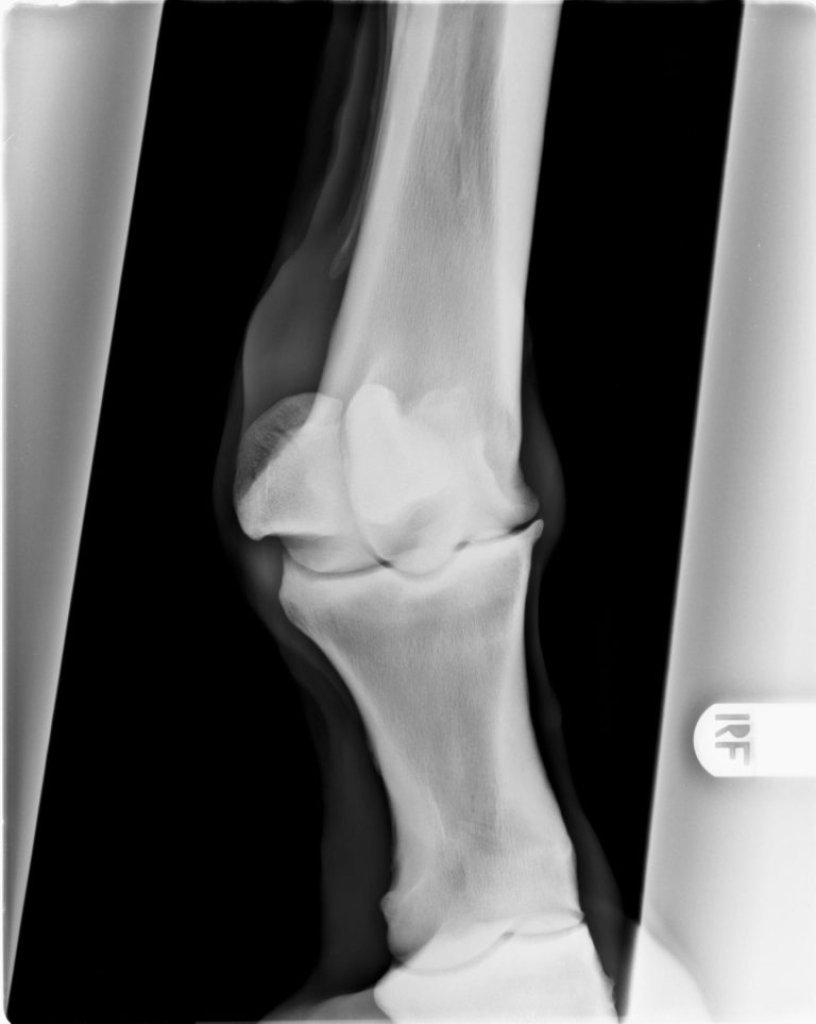

Röntgenopname van een gewricht met artrose

Uitvergroting van hetzelfde gewricht.

Door een kleine beschadiging kan uiteindelijk soort vicieuze cirkel ontstaan waarbij de kwaliteit van het kraakbeen langzaam aan steeds slechter wordt. Als gevolg van de schade aan het kraakbeen gaat ook het onderliggende bot reageren, het gaat aan de randen van het gewricht nieuw bot vormen. Dit is op een röntgenfoto goed zichtbaar als scherpe randjes of bot nieuwvormingen rond het gewricht. Het kraakbeen zelf is helaas niet in beeld te brengen met röntgenfoto’s, daarom is op een röntgenfoto in een heel vroeg stadium van artrose nog niks zichtbaar.

De diagnose van artrose is te stellen op basis van röntgenfoto’s. Op de röntgenfoto’s zien we bij artrose vaak veranderingen aan de randen van de gewrichten. Meestal ontstaan er scherpe randen rond het gewricht.